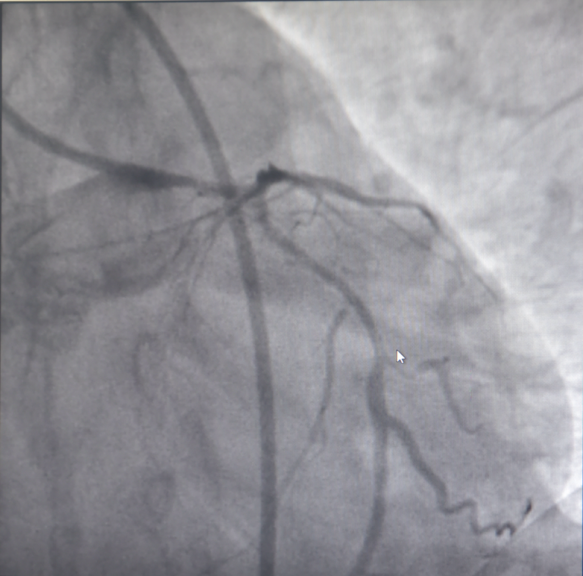

随后,患者立即被送往导管室,揭主任携副主任医师蒋溢为迅速给患者完成了冠脉造影,术中见患者左主干明显变窄,回旋支闭塞,血流TIMI0级,前降支次全闭塞,血流TIMI1级。但此时尚未能明确患者是否为冠脉痉挛或冠脉自发夹层,揭英纯和蒋溢为副主任医师当机立断,为患者快速完成了血管内超声检查,原来是冠状动脉自发夹层!考虑到患者冠脉已经闭塞,遂在IVUS指导下选择切割球囊精准对闭塞血管进行切割扩张,恢复回旋支及前降支正常血流。

血管再通,血流恢复正常